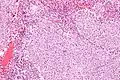

| Micrograph of a glassy cell carcinoma of the cervix. H&E stain. | |

Glassy cell carcinoma of the cervix, also glassy cell carcinoma, is a rare aggressive malignant tumour of the uterine cervix.[1] The tumour gets its name from its microscopic appearance; its cytoplasm has a glass-like appearance.

Under the microscope, glassy cell carcinoma tumours are composed of cells with a glass-like cytoplasm, typically associated with an inflammatory infiltrate abundant in eosinophils and very mitotically active. PAS staining highlights the plasma membrane.[2]

Low mag.

Low mag. High mag.